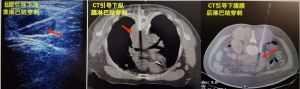

人们根据淋巴结肿大——“烽火台”报警,一般就可弄清淋巴结肿大的原发病灶。必要时还应当进行X线摄片、病理切片镜检、B超及CT等特殊检查。这样“顺藤摸瓜”和综合分析,躲在背后的病魔自然会原形毕露。

淋巴结因内部细胞增生或肿瘤细胞浸润而体积增大的现象。临床常见的体征。可通过触摸颌下、颈部、锁骨上窝、腋窝和腹股沟等部位

而发现,但肺门、纵隔、腹膜后和肠系膜等体内肿大的淋巴结则要靠X射线、CT和B超等才能发现。淋巴结肿大常见3种情况:①良性肿大。包括各种感染、结缔组织病和变态反应等引起的肿大。临床常呈良性经过,随着病因去除,在一定时间内可以完全恢复。②恶性肿大。包括原发于淋巴结的恶性肿瘤如淋巴瘤、淋巴细胞性白血病和恶性组织细胞病等及其他恶性肿瘤的淋巴结转移如肺癌、胃癌和乳腺癌等。临床呈恶性经过,淋巴结持续性进行性肿大,若不积极治疗,常会进行性恶化死亡。③介于良性与恶性间的肿大。如血管原始免疫细胞性淋巴结病和血管滤泡性淋巴结增生症等。开始常为良性,可变成恶性而致命。因此在确定淋巴结肿大后,关键是确定其原因和性质,局部肿大伴明显疼痛者常提示感染;进行性无痛性肿大者常提示恶性肿瘤性疾病。骨髓穿刺特别是淋巴结活检可帮助确诊。淋巴结肿大的治疗以病因而定,如淋巴腺结核可应用链霉素和雷米封等,若为恶性淋巴瘤,应以联合化疗为主,若为癌症晚期转移,则预后极差。